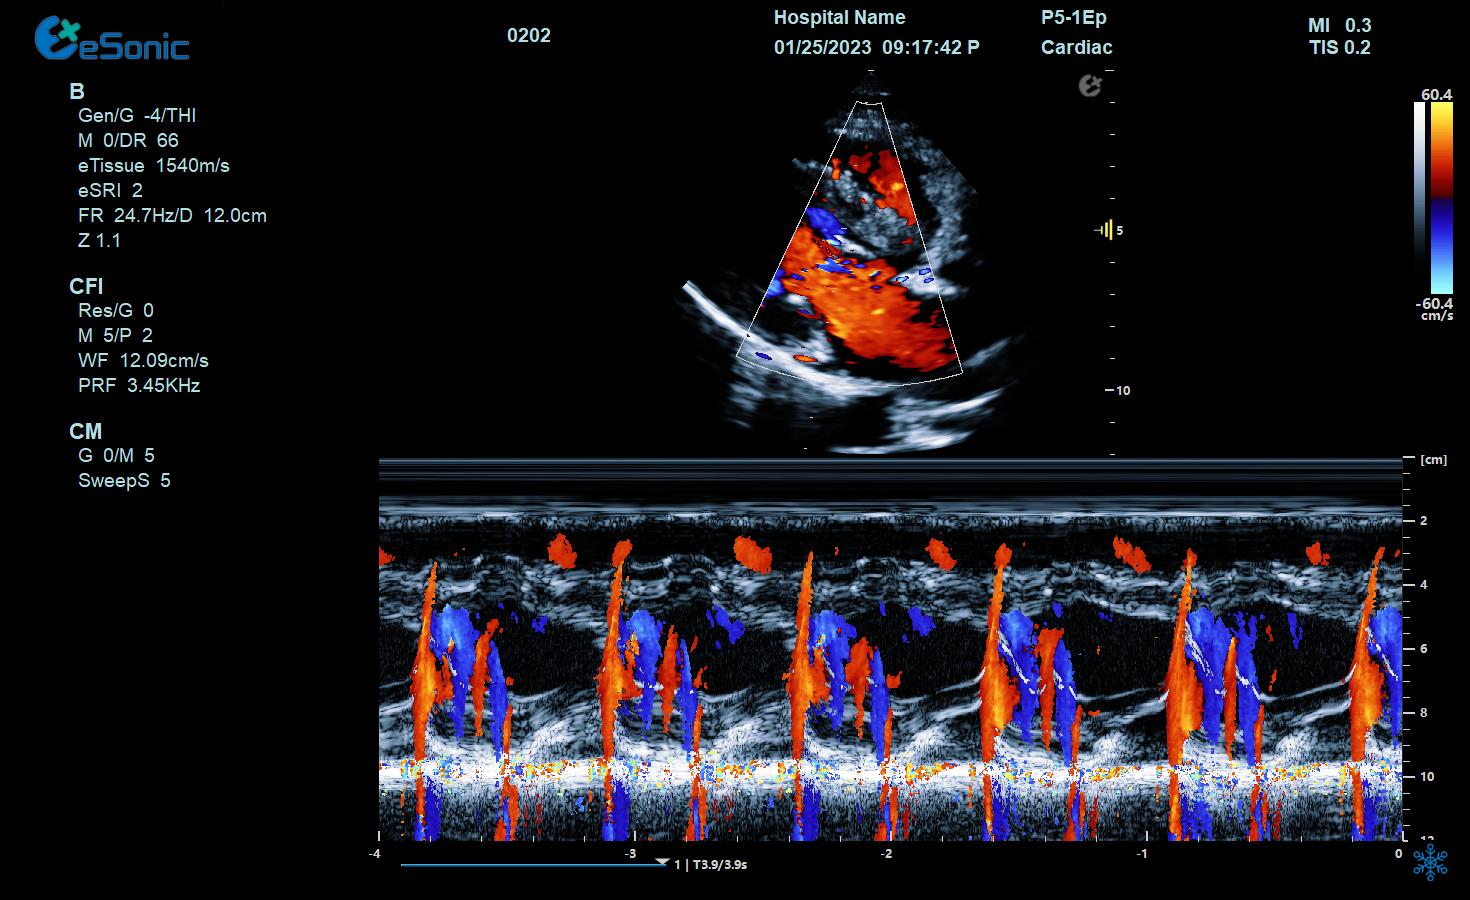

男性,6岁,临床诊断:先心病 室间隔缺损

超声表现:室间隔膜周部可见回声中断;CDFI显示左向右过隔血流信号。

室缺(膜周)